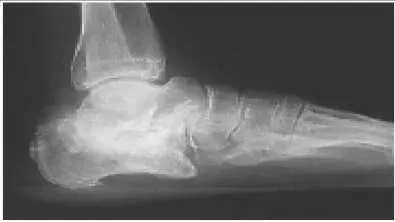

A patient sustained a fracture of the calcaneus 9 months ago. The fracture was treated with non-weight bearing and cast immobilization. The patient experiences constant pain and is unable to work. On examination, he has limited inversion, eversion motion of the foot, and lateral foot pain. Radiographs are presented. The recommended treatment is:

Correct Answer: Subtalar arthrodesis

In the presence of stiffness of the subtalar joint, physical therapy modalities are unlikely to improve the foot function. For the young active worker, an early subtalar arthrodesis is the most reliable procedure to return him to work and an active lifestyle. A triple arthrodesis is contraindicated in the absence of painful transverse tarsal arthritis.